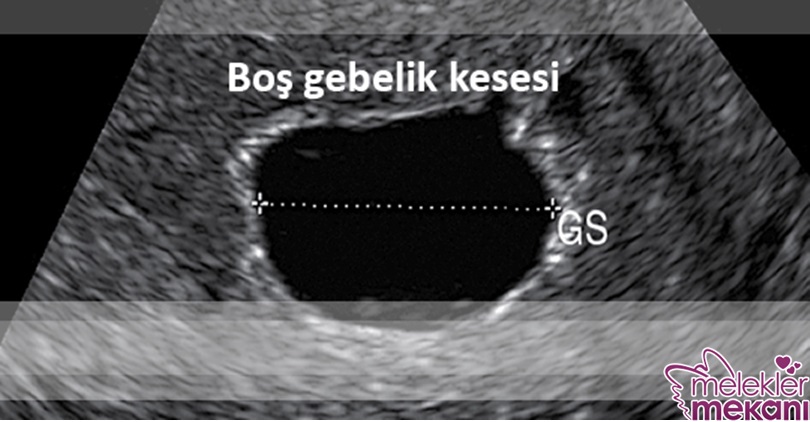

Bir kadın gebe kaldığında fertilize olmuş yumurta ( blastokist ) rahim duvarına yapışır. 6 haftalık iken ultrasonda embriyo görülmelidir. Bu sürede gebelik kesesi yaklaşık olarak 18 mm çapındanır. Boş gebelikte ise gebelik kesesinin çapı büyümeye devam ettiği halde embriyonun gelişimi devam edemez.

Ultrasonografi boş gebelik tanısı için gereklidir. Ultrasonografide gebelik kesesi içerisinde embriyonun görülmemesi ( boş kese ) tanıyı destekler.